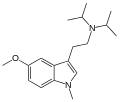

| MiPT | artificial | H | CH3 | CH(CH3)2 | N-Methyl-N-isopropyltryptamine | 96096-52-5 |